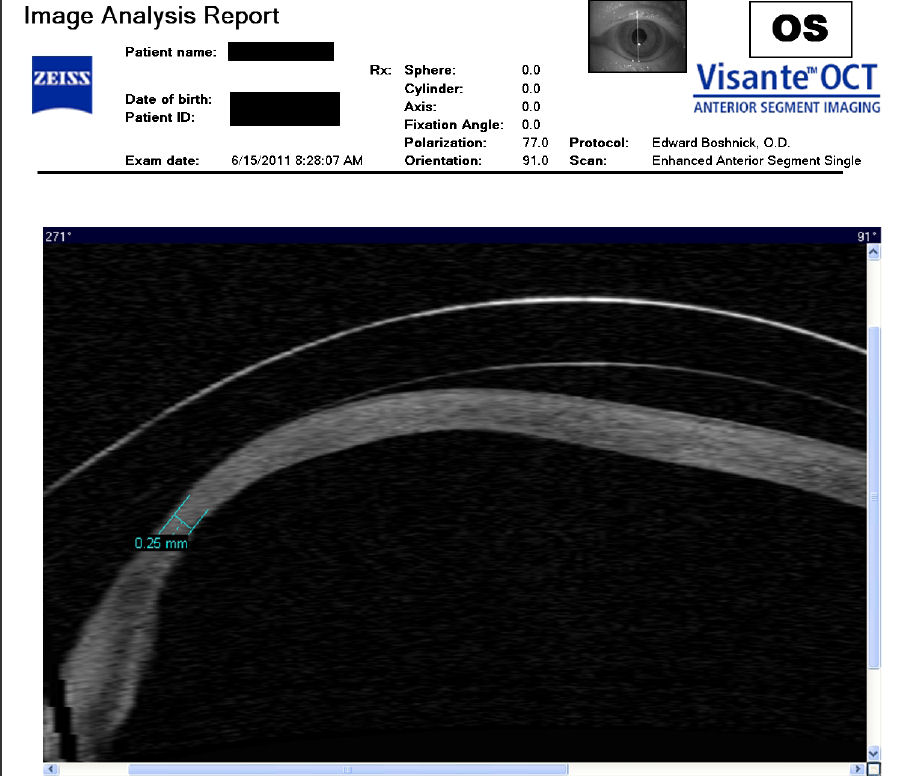

Следующие изображения были получены с использованием метода, называемого оптической когерентной томографией, или ОКТ. Прибор позволяет получить изображение в поперечном сечении путем сканирования передней части глаза (переднего сегмента) лучом света. Думайте об этом как об ультразвуке, использующем свет вместо звуковых волн для создания изображения живых тканей.

На изображении, приведенном непосредственно ниже, представлен снимок здоровой, неоперированной роговицы для сравнения со следующими изображениями эктатических роговиц после операции LASIK.

На снимке ниже показана эктазия роговицы после операции LASIK. Толщина роговицы в самом тонком месте составляет всего 250 микрон, что в два раза меньше толщины нормальной роговицы. Пациент носит большие терапевтические контактные линзы. Белая изогнутая линия вверху обозначает переднюю поверхность хрусталика. Ниже расположена более слабая белая изогнутая линия, обозначающая заднюю поверхность хрусталика. Между хрусталиком и роговицей находится пространство, заполненное физиологическим раствором, который имеет зернистый вид. Нажмите на изображение, чтобы увеличить его.

На изображении ниже представлен снимок роговицы в поперечном сечении после операции LASIK. Белая изогнутая линия вверху - это передняя поверхность твердой контактной линзы. Следующая едва заметная белая линия - это задняя поверхность линзы. Следующая область, которая имеет зернистый вид, - это пространство между хрусталиком и роговицей, заполненное физиологическим раствором. Роговица имеет классические признаки эктазии - истончение, выпуклость и неправильную форму.

На снимке ниже показана роговица пациента, у которого после операции LASIK развилась эктазия. Пациент носит жесткие склеральные контактные линзы. Вы можете видеть выпячивание роговицы в самом слабом месте (эктазия), что приводит к сильному искажению зрения. Очки и мягкие контактные линзы неэффективны для таких глаз, как этот. Нажмите на изображение, чтобы увеличить.

Изображения любезно предоставлены доктором Эдвардом Бошником, который посвятил свою практику восстановлению качественного зрения и информации о эктазия после операции LASIK .